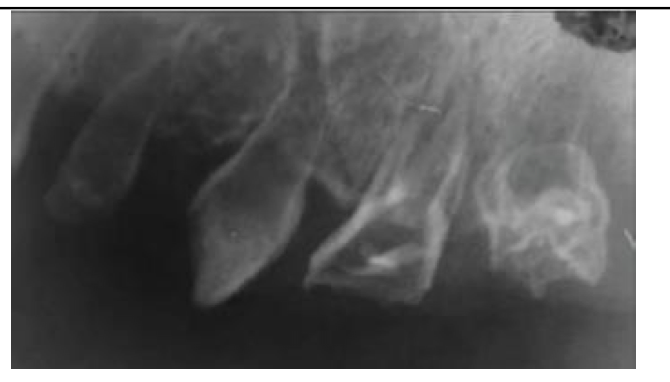

Dentinogenesis Imperfecta

A

Autosomal Dominant

Intrinsic alteration of DENTIN in primary & permanent teeth

* SHOrt roots, bell shaped crowns, & obliterated pulps

* Bulbous crowns in radiographs (Bc constricted DEJ)

* Blue sclera

Tx: Full Coverage crowns